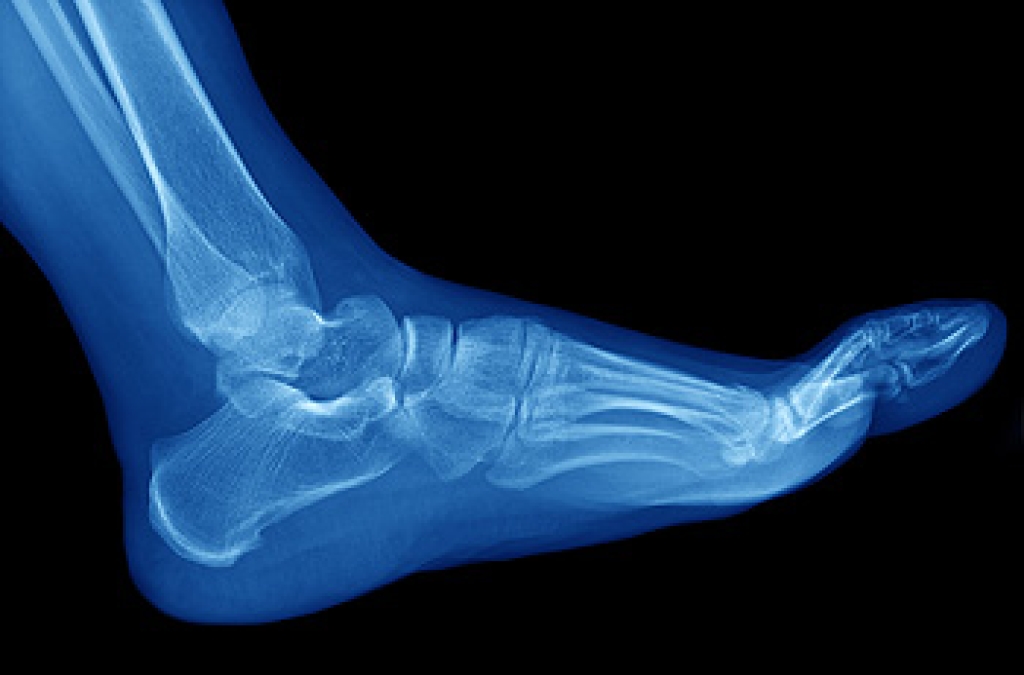

A stress fracture is a broken bone. There are several types of fractured bones, and stress or hairline fractures generally happen gradually. The feet are a common place for stress fractures which typically result from overuse. People who enjoy running may experience stress fractures, but they may be prevented when proper warming up and cooling down are practiced. Research has shown that people who frequently wear high heels or other shoes that do not fit correctly may develop stress fractures from the consistent pressure the feet endure. Additionally, this type of fracture may happen from increasing running speed and distance too soon, as the feet need time to adapt. Patients who perform weight training on opposite days may notice their bodies becoming stronger, and running can become easier. If you develop a stress fracture, it is strongly suggested that you speak with a podiatrist who can provide the best treatment for you.

Stress fractures are the result of repetitive force being placed on the bone. Since the lower leg and feet often carry most of the body’s weight, stress fractures are likely to occur in these areas. If you rush into a new exercise, you are more likely to develop a stress fracture since you are starting too much, too soon. Pain resulting from stress fractures may go unnoticed at first, however it may start to worsen over time.